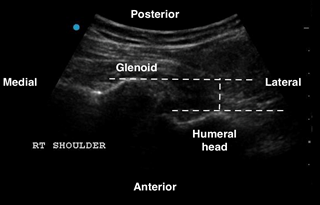

In the shoulder POCUS, a posterior approach allows the visualization of the humeral head in relation to the glenoid fossa. The following are the steps to perform in order to obtain this view.

- The scapular spine can be identified as a hyperechoic line with a posterior shadow. Note that the deltoid and the infraspinatus muscles can be seen above the scapular spine (See Figure 1).

- Continue sliding the probe laterally along the scapular spine towards the glenohumeral joint (GHJ), until visualizing the glenoid fossa which is closely followed by the humeral head (See Figure 1). Positioning the glenoid fossa and the GHJ in the center of the screen while adjusting the depth, will result in a better image quality. Asking the patient to externally and internally rotate the affected shoulder will aid in identifying the humeral head (See Figure 2).

Figure 1: Normal right shoulder